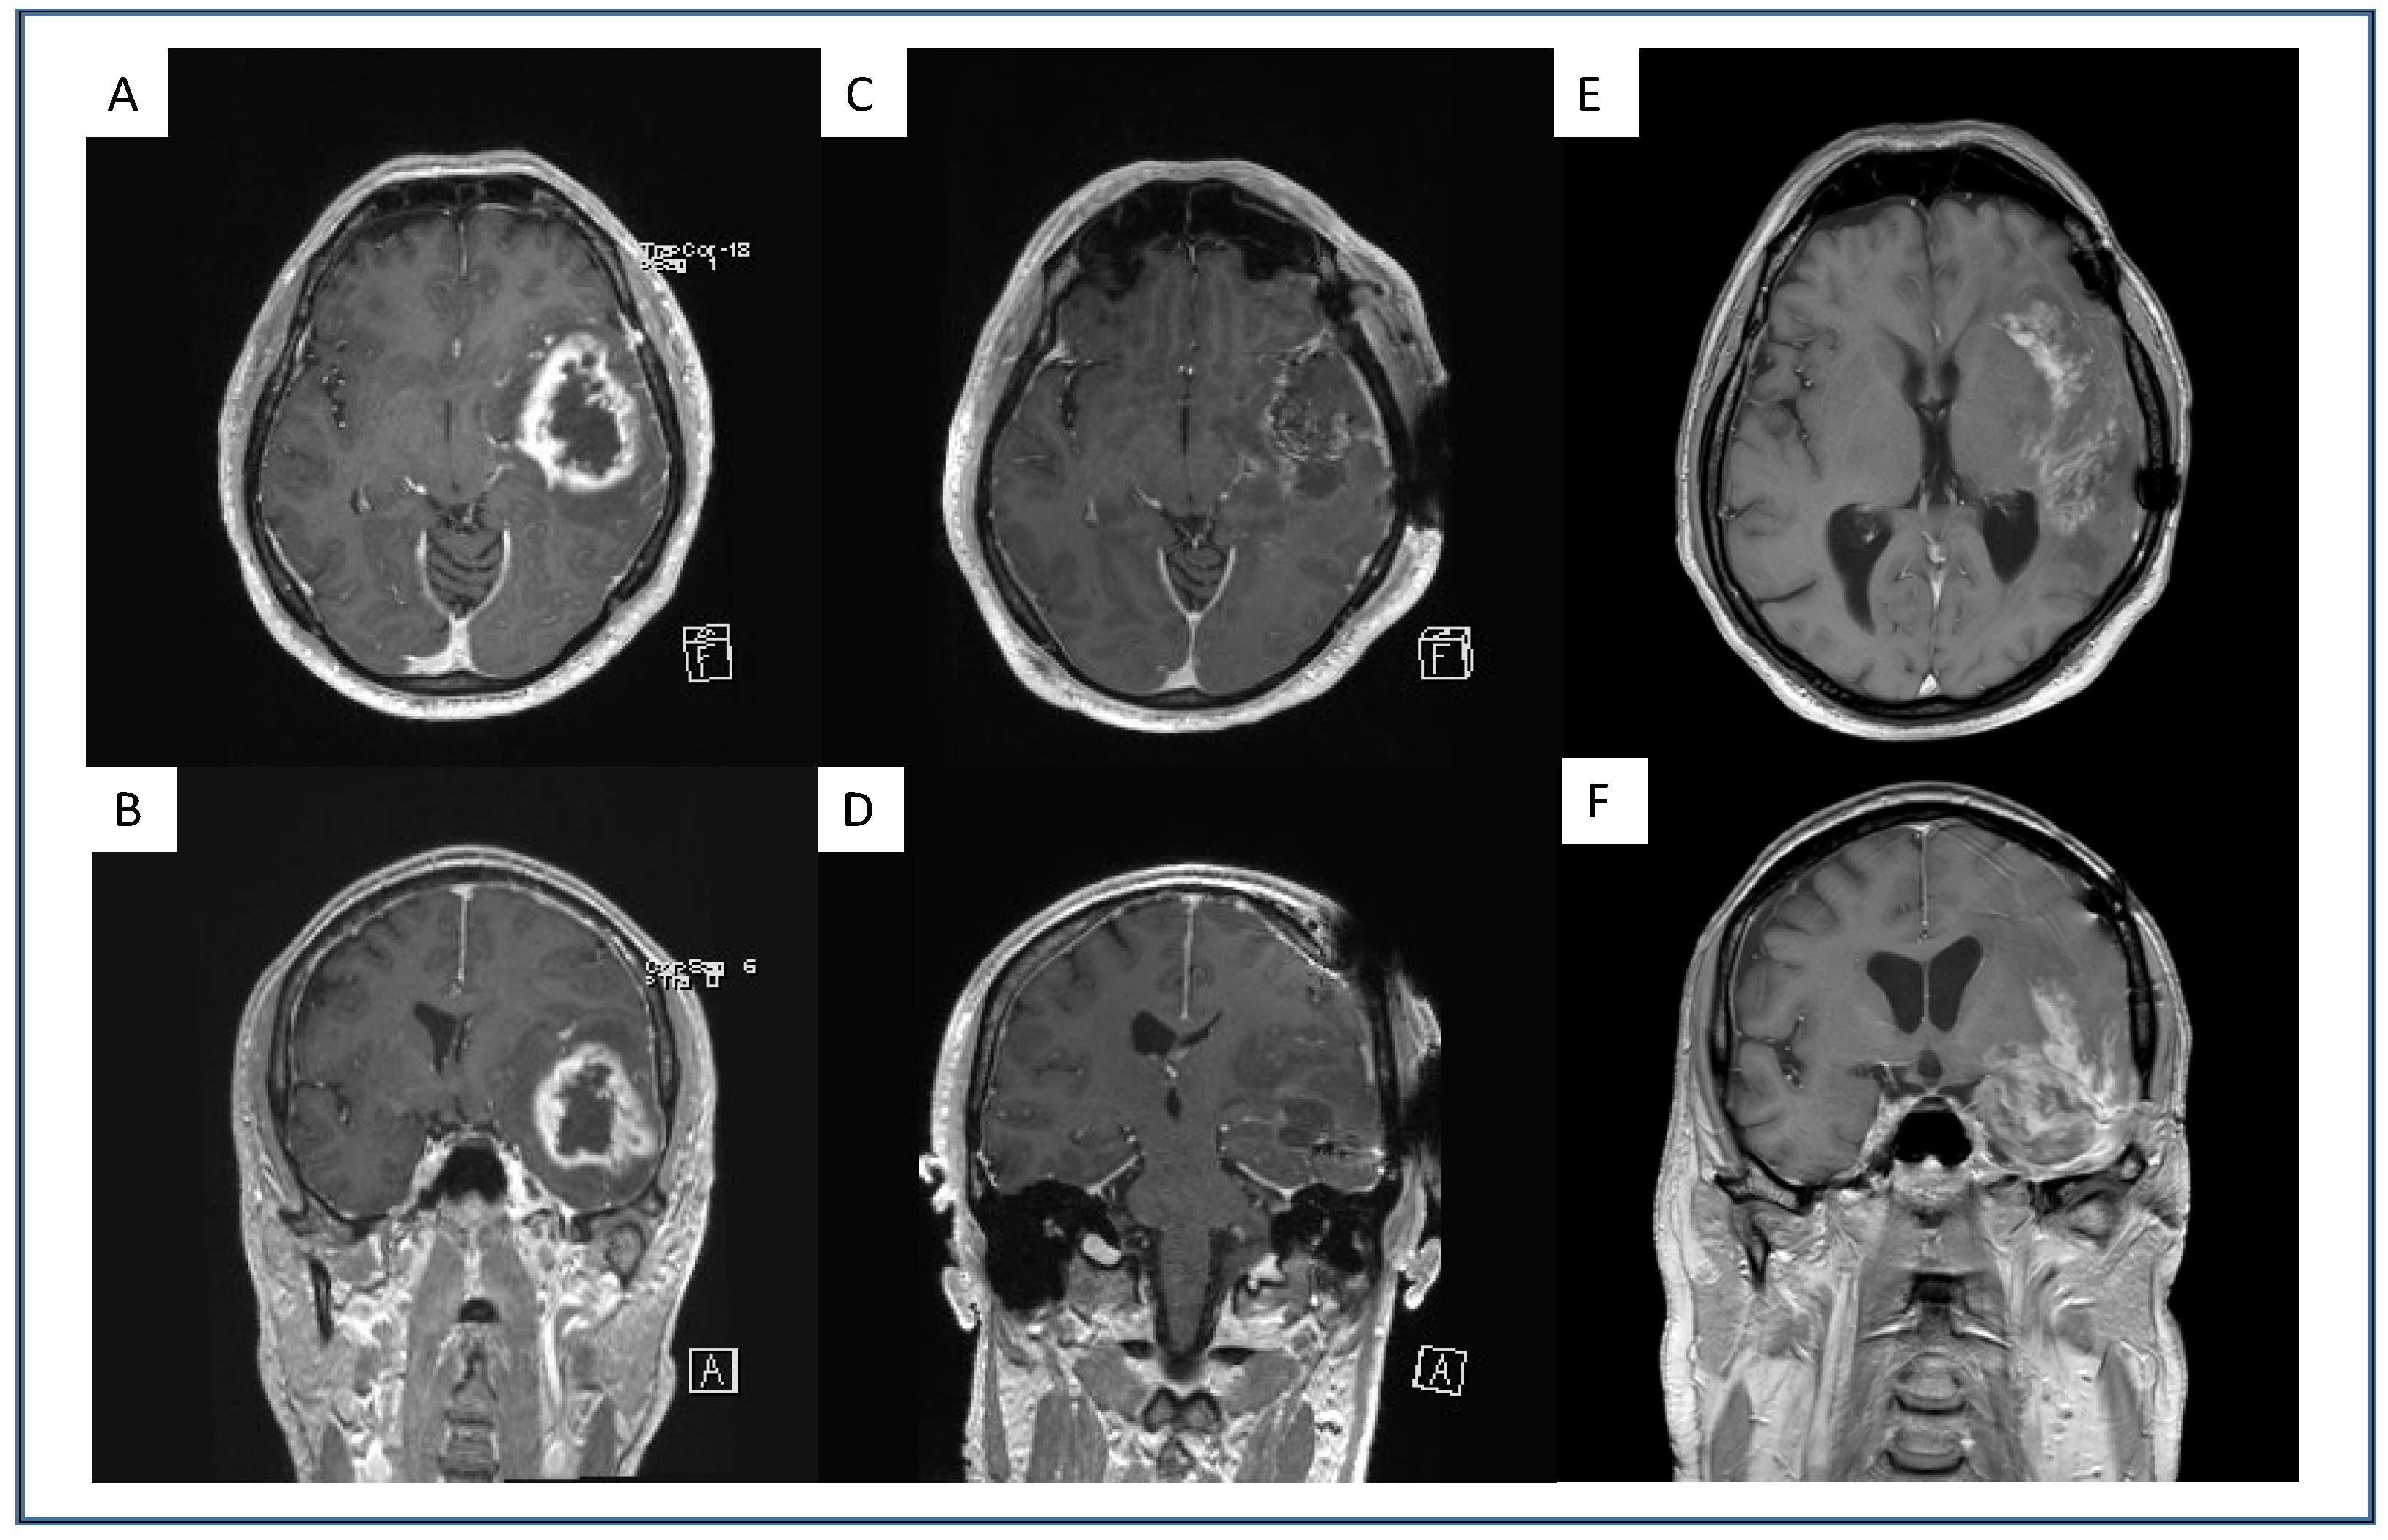

4.1. Multifocal and Midline-Crossing Relapse

4.2. Sharp Demarcated Lesions

4.3. Analysis of Intratumoral Hemorrhage